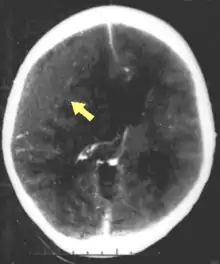

الأورام الدموية، هي أيضًا إصابات بؤرية، وهي عبارة عن تجمعات من الدم في أو حول الدماغ يمكن أن تنتج عن النزف.[3] النزيف المخي هو آفة داخل المحور نفسه حيث تنزف أنسجة المخ نفسها. بينما تشمل الآفات خارج المحور الورم الدموي فوق الجافية، الورم الدموي تحت الجافية، ونزف تحت العنكبوتية، والنزيف داخل البطين.[31] ينطوي الورم الدموي فوق الجافية على نزيف في المنطقة بين الجمجمة والأم الجافية، الغشاء الخارجي من الأغشية الثلاثة المحيطة الدماغ.[3] وفي الورم الدموي تحت الجافية، يحدث النزيف بين الأم الجافية والأم العنكبوتية.[15] بينما ينطوي نزف تحت العنكبوتية على النزيف في الفضاء بين الغشاء الأم العنكبوتية والأم الحنون.[15] ويحدث النزيف داخل البطين عندما يكون هناك نزيف في الجهاز البطيني.[31]

وتشمل اضطرابات الحركة التي قد تتطور بعد الإصابة الدماغية الرضية: الرعاش، والرنح (حركات العضلات غير المنسقة)، والرمع العضلي (تقلصات تشبه الصدمة في العضلات)، وفقدان نطاق الحركة والسيطرة.[84] ويزداد خطر الصرع التالي للرض مع شدة الرضة (الصورة في اليسار) ويزداد بشكل خاص مع أنواع معينة من صدمات الدماغ مثل الكدمات الدماغية أو الورم الدموي.[107] الأشخاص الذين يعانون من التشنجات المبكرة، تلك التي تحدث في غضون أسبوع من الإصابة، لديهم خطر متزايد من الصرع التالي للرضة (النوبات المتكررة التي تحدث بعد أكثر من أسبوع من الصدمة الأولية).[116] كما قد يفقد أو يعاني المصابون من تغير البصر أو السمع أو الشم.[3]